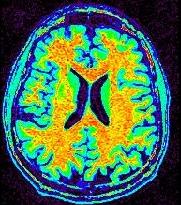

L'image IRM brute et sa version corrigée du biais vont apparaÎtre dans Anatomist dotées d'une table de couleur arc-en-ciel. En jouant sur le réglage de la table de couleur, vous pouvez prendre conscience du biais dans l'image initiale (en général, l'image est plus claire au centre du champ de vue) :

En revanche, cet effet doit avoir disparu après la correction. Pour s'en convaincre, il faut pouvoir régler la table de couleur de manière à faire apparaître la matière blanche comme un mélange régulier de jaune et de rouge :